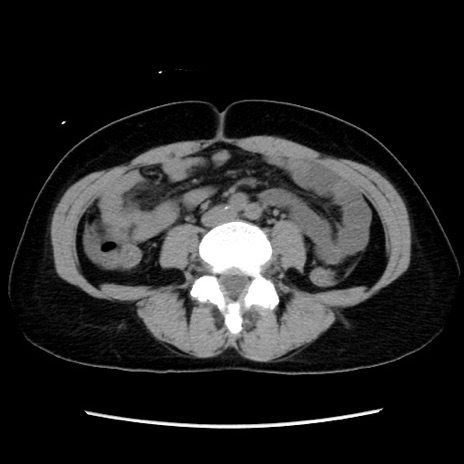

冠状断像